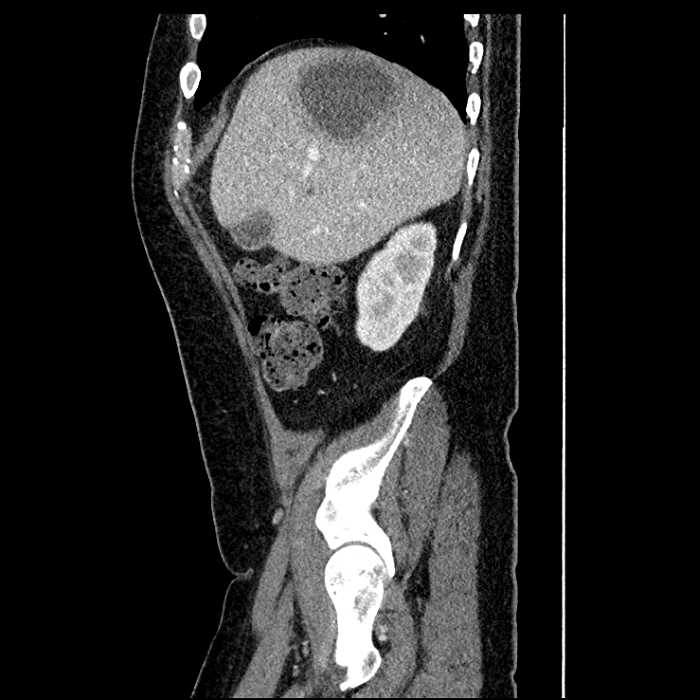

• Large fluid density structure in hepatic segments 7 and 8 measuring 10 x 7 x 7 cm with internal septation and circumferential ill-defined low density compatible with edema

• Peripherally enhancing subcapsular collections along the anterior margin of the left hepatic lobe measuring 3 x 1 cm and 2 x 1 cm

• Clearly marginated fluid density structure in segment 7 and several other scattered tiny hypodensities, which likely represent cysts

• Mild mural thickening of a segment of the sigmoid colon with adjacent fat stranding and a 1.5 cm fluid and gas collection along the tip of an inflamed diverticulum

Acute sigmoid diverticulitis complicated by a small contained perforation and a large abscess in the right hepatic lobe. Additional small subcapsular abscesses along the anterior margin of the left hepatic lobe.

Additionally, loss of the normal fat plane between the peridiverticular collection and adjacent thickened loops of small bowel raises the potential for an enterocolonic fistula.

• The classic CT imaging appearance is a double target sign with internal low density surrounded by an internal enhancing rim (capsule) and a low density external rim (edema)

Hepatic abscess showing the double target sign with low density internally surrounded by a thin inner enhancing rim (red arrow) and ill-defined outer low density rim (yellow arrow). Blue arrow indicates an internal septation. Red arrows: additional smaller subcapsular abscesses. Red arrow: focal contained perforation associated with diverticulitis.